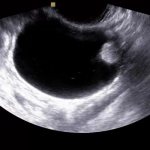

Киста почки – доброкачественное полостное образование на одной или обеих почках, которое имеет капсулу